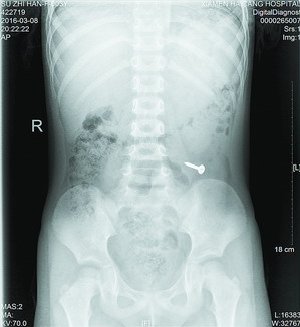

当天值班的叶医生了解情况后,马上安排小桐做X光片检查,检查影像一出来,大家都吓了一跳,只见小桐左下腹清晰地躺着一个金属异物。经与小桐再三辨认,确定是一颗螺丝钉。外科徐医生接诊后表示,患者年龄太小,手术损伤大,且目前没有腹痛、腹膜炎等肠穿孔征象,螺丝钉不是很大,有可能自行排出,便建议随访,让患儿多吃些富含纤维素的食物,如韭菜、芹菜,以促进消化道蠕动,加速螺丝钉的排出。同时,医生告知小桐父母需密切观察大便中是否有钉子排出,如有呕血、腹痛、发烧等异常情况,需马上就医。3天后,小桐再来海沧金沙集团 拍片复查,发现螺丝钉已经顺利排出了,虚惊一场。